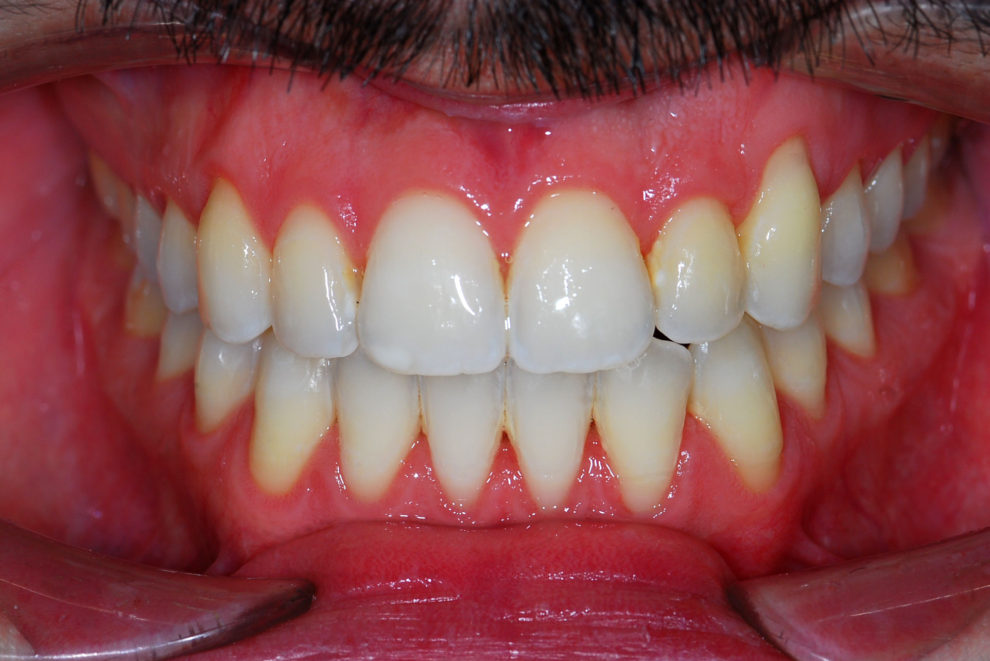

Ortodoncia + Mordida abierta

Nuestro paciente Manuel Vergara Gil acudió a nuestra clínica, y se le hizo una Ortodoncia.